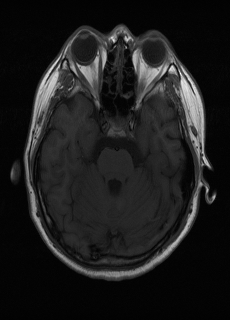

λT1=6.63subscript𝜆subscript𝑇16.63\lambda_{T_{1}}=6.63 Refer to caption (a) 34.38/0.9371 Refer to caption (b) 42.42/0.9883 Refer to caption (c) 44.60/0.9920 Refer to caption (d) 45.50/0.9940 Refer to caption (e) PSNR/SSIM

λT2=2.11subscript𝜆subscript𝑇22.11\lambda_{T_{2}}=2.11 Refer to caption (f) 29.74/0.8903 Refer to caption (g) 36.25/0.9734 Refer to caption (h) 36.42/0.9752 Refer to caption (i) 37.70/0.9832 Refer to caption (j) PSNR/SSIM

λflair=8.00subscript𝜆𝑓𝑙𝑎𝑖𝑟8.00\lambda_{flair}=8.00 Refer to caption (k) 39.89/0.9311 Refer to caption (l) 43.94/0.9864 Refer to caption (m) 44.74/0.9883 Refer to caption (n) 45.49/0.9894 Refer to caption (o) PSNR/SSIM

Figure 3: Visual comparison of different methods, with PSNR (dB) and SSIM values listed under the images. After recovery, the images are shaper with more visible details.